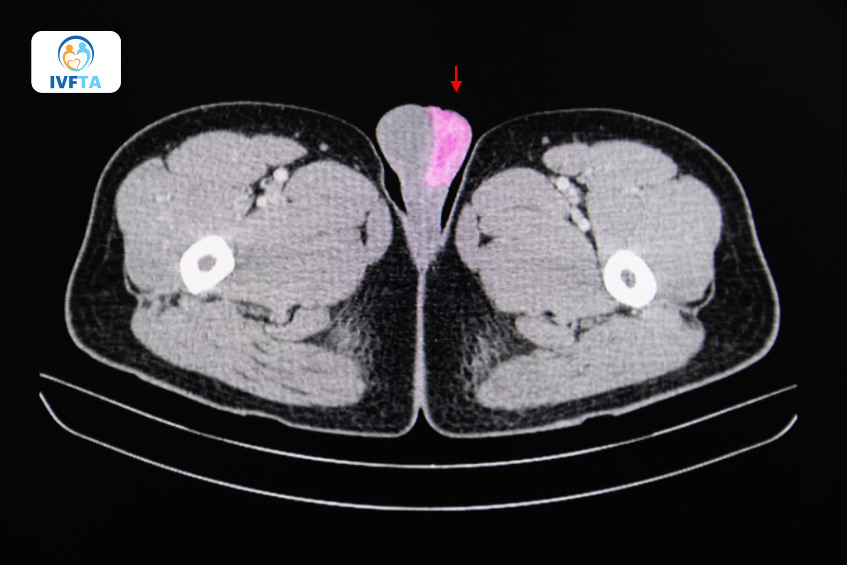

Khi kết quả xét nghiệm nghi ngờ có u tinh hoàn ác tính, bác sĩ sẽ yêu cầu người bệnh thực hiện chụp CT vùng ngực, bụng và bẹn để đánh giá xem khối u có di căn sang cơ quan hoặc mô xung quanh hay chưa, qua đó xác định mức độ lan rộng của u tinh hoàn và đưa ra hướng điều trị phù hợp.